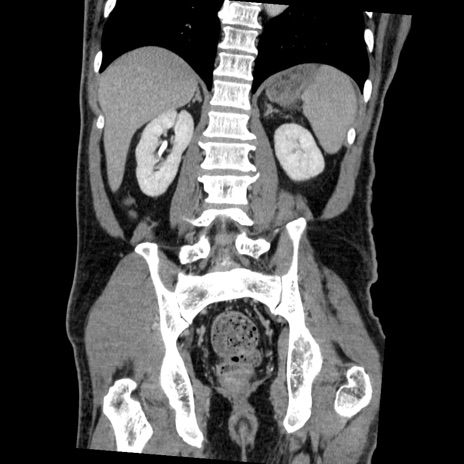

症例22(冠状断像)

【症例】50歳代男性

【主訴】腹痛

【現病歴】AVMからの被殻出血のため回復期リハ病棟入院中。 本日午後3時頃急に下腹部痛が出現した。

【既往歴】AVM、被殻出血、虫垂炎、高血圧

【身体所見】意識晴明、左半身不全麻痺、会話の理解は良好、36.5°C、腹部:膨隆、全体に板状硬、下腹部正中に圧痛点あり、反跳痛-、筋性防御不明、右下腹部にope scar

【データ】WBC 9400、CRP 0.06